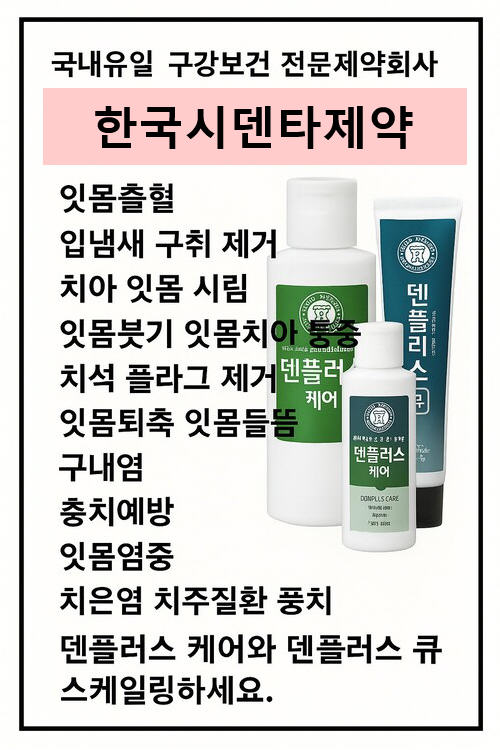

덴플러스를 사용하고, 새 잇몸이 생겼어요!

저와 남편은 평소 잇몸이 약해 잇몸 염증과 입냄새로 오랜 시간 고생했습니다.

처음에는 큰 기대 없이 사용했지만, 4개월간 꾸준히 사용한 지금은 치과에서도 놀랄 만큼 큰 변화를 경험했습니다.

최근 치과에 갔을 때, 의사 선생님께서 남편의 인공치아 주변에 새 잇몸 조직이 형성되었다는 말씀을 하셨습니다.

저희는 하루 세 번 실리콘 칫솔로 부드럽게 잇몸을 닦고, 낮 시간에는 치약을 약한 부위에 발라 10분 정도 유지하는 방법을 병행했습니다.

덴플러스는 잇몸 조직 재생, 구강 상쾌함 유지, 입냄새 제거에 탁월한 제품입니다.

저희처럼 오랜 시간 잇몸 문제로 고민하신 분들께 강력히 추천드립니다. |